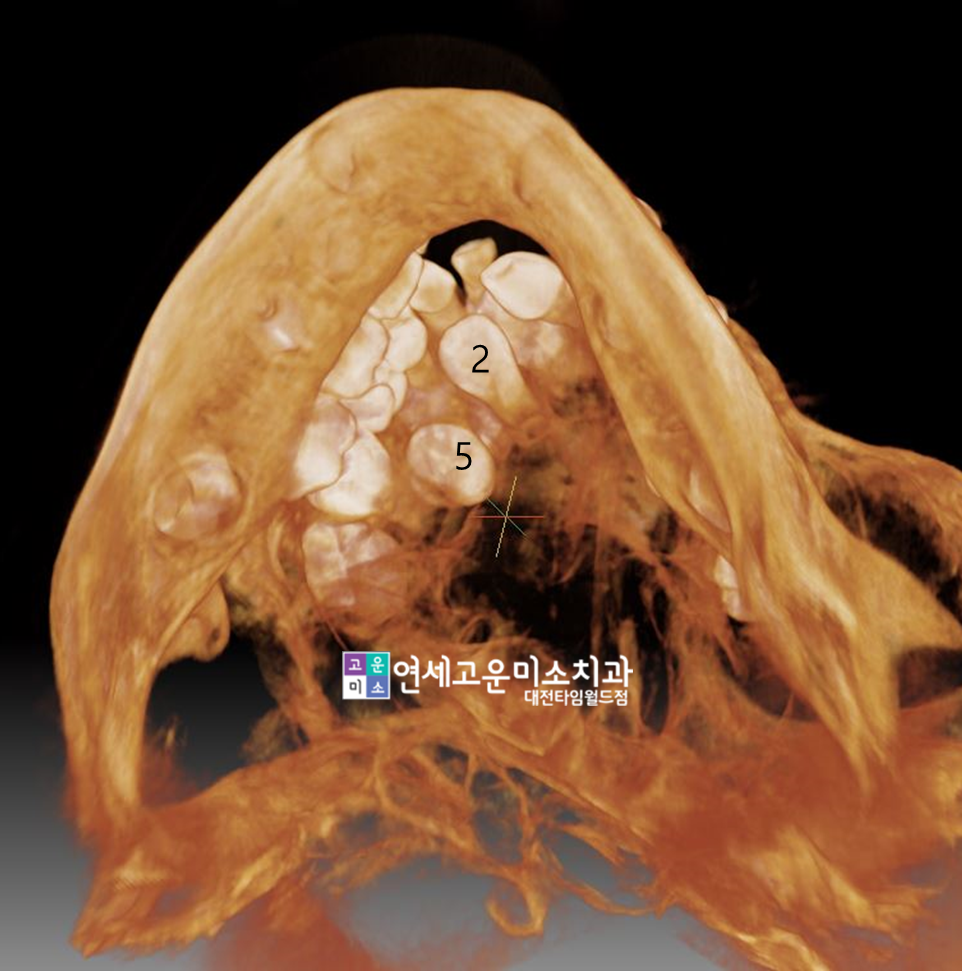

CT를 찍어서 다시 한번 확인했습니다

근데 대반전!

1번 자리의 치아는 과잉치인데,

보통 과잉치는 매복되어 있어서

맹출하지 않는 경우가 많습니다만,

과잉치가 1번 자리로 내려왔습니다.

과잉치인 1번치아는 2번자리 바깥에서

나오고 있는것을 확인할 수 있습니다

모양도 정상적이구요.

3번 4번도 바깥쪽에서 보입니다

그렇다면 2번 5번은?

보이지 않았던 5번은 안쪽에서

방향이 잘못되서 나오고 있었네요.

정말 다행스럽게도 이런 경우에는

과잉치를 발치하고 나머지 치아들을

전부 제위치 시켜줄 수 있는

상황인 것이 확인되었습니다.

물론 나중에 앞니를 씌우는 치료도

하지 않아도 되구요. ^^